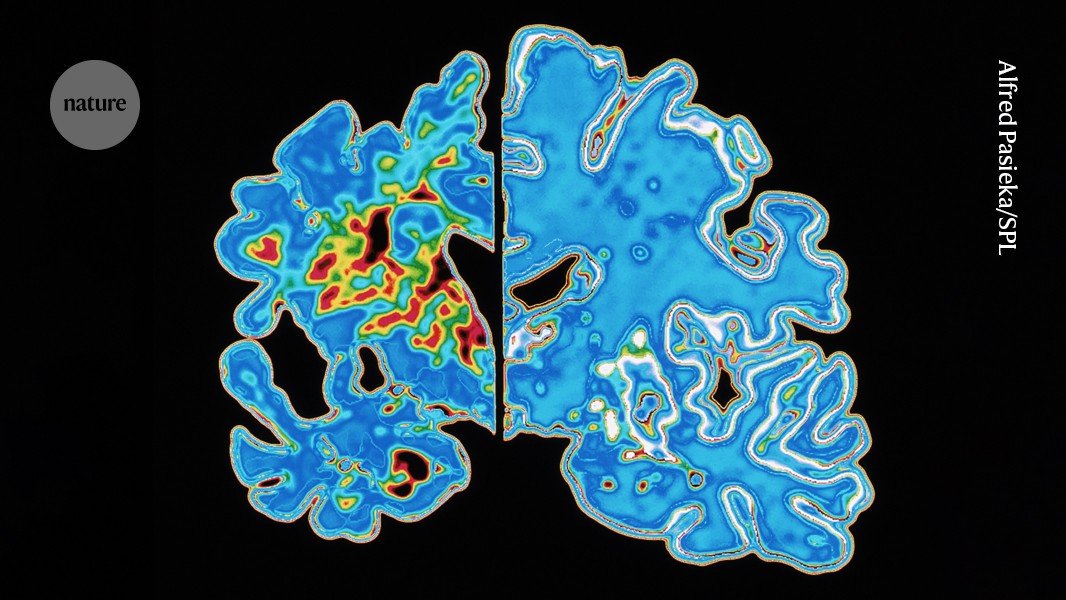

Abnormal tau proteins can form tangled fibres that accumulate in the brains of people with Alzheimer’s (slice at left). (Brain without Alzheimer’s shown at right.)Credit: Alfred Pasieka/Science Photo Library

Abnormal tau proteins can form tangled fibres that disrupt communication among the brain’s nerve cells. Brain-imaging tests that detect tangled tau are sometimes used when diagnosing Alzheimer’s, and preliminary studies suggest that such tests might also be able to predict when a person’s Alzheimer’s symptoms will appear2,3.